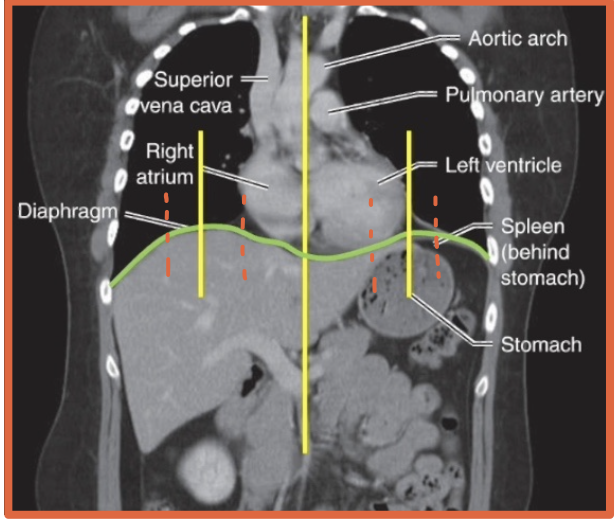

What is the mediastinum?

The space between the lungs bounded by the sternum anteriorly and spine posteriorly

What major structures are in the mediastinum?

Heart

Great vessels

Trachea

Esophagus

All have similar radiodensity, besides air filled

What mainly forms the right mediastinal border?

Superior vena cava

Right atrium

What are the three major bumps on the left mediastinal border?

Aortic arch or knob

Left atrial appendage

Left ventricle